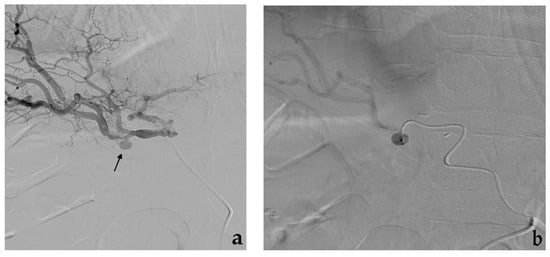

3.1. Coil Embolization

- Koganemaru, M.; Abe, T.; Nonoshita, M.; Iwamoto, R.; Kusumoto, M.; Kuhara, A.; Kugiyama, T. Management of visceral artery embolization using 0.010-inch detachable microcoils. Diagn. Interv. Radiol. 2014, 20, 345–348. [Google Scholar] [CrossRef] [PubMed]

- Yasumoto, T.; Osuga, K.; Yamamoto, H.; Ono, Y.; Masada, M.; Mikami, K.; Kanamori, D.; Nakamura, M.; Tanaka, K.; Nakazawa, T.; et al. Long-term outcomes of coil packing for visceral aneurysms: Correlation between packing density and incidence of coil compaction or recanalization. J. Vasc. Interv. Radiol. 2013, 24, 1798–1807. [Google Scholar] [CrossRef] [PubMed]